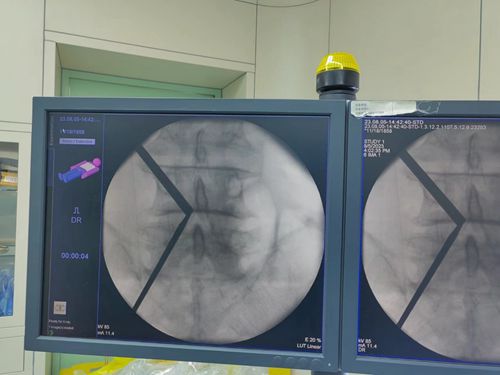

入院后完善相關(guān)術(shù)前檢查,經(jīng)過術(shù)前充分的溝通和準(zhǔn)備,骨二科團(tuán)隊(duì)為患者進(jìn)行了單側(cè)雙通道(UBE)脊柱內(nèi)鏡下陳舊性復(fù)發(fā)性椎管減壓松解椎間盤切除手術(shù)的治療。手術(shù)在全麻下進(jìn)行,精準(zhǔn)定位開兩個(gè)1.5CM的觀察口及操作口進(jìn)入內(nèi)鏡,徹底減壓、松懈神經(jīng)根,僅用時(shí)90分鐘手術(shù)順利完成,術(shù)中出血僅15毫升,術(shù)后患者腰痛及右下肢疼痛、麻木癥狀明顯好轉(zhuǎn),取得滿意的治療效果。